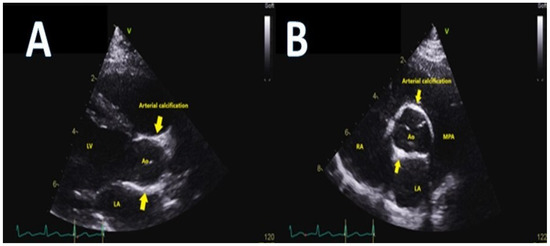

- Kutty, S.; Cava, J.R.; Frommelt, M.A. Idiopathic infantile arterial calcification: A case report of prenatal and postnatal echocardiographic diagnosis. Echocardiography 2009, 26, 862–864. [Google Scholar] [CrossRef]